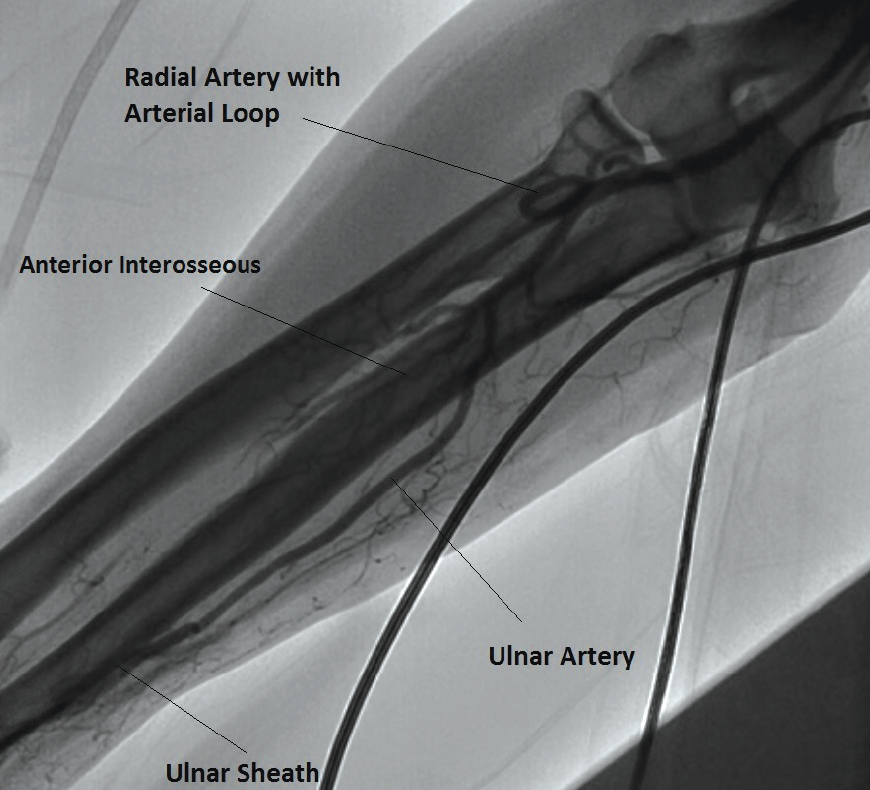

Similar to TRA, the shortest and smallest-diameter sheath should be used to minimize the risk of arterial injury and patient discomfort. Proximal ulnar artery thrombosis can potentially affect the anterior interosseous artery (which stems from the proximal ulnar artery), which is the predominant collateral to the lateral aspect of the wrist in case of radial artery occlusion (Figure 2). Therefore, if the radial artery is known to be occluded, the presence of collateral circulation to the lateral aspect of the wrist should be routinely assessed by injecting contrast into the accessed ipsilateral ulnar artery.

After cannulation of the ulnar artery, a soft-tip, 0.018-inch guidewire, preferably with a mildly angled tip, is introduced, over which a sheath with dilator is advanced (Figure 2). A 5- or 6-F sheath is suitable for PCI, and a 4- or 5-F sheath is preferred for diagnostic angiography. The sheath can be partially inserted into the ulnar artery especially when resistance is encountered. Sheath fixation by either suturing or fixation with Tegaderm (3M Medical) can limit the sheath movement. Routine vasospasm should be mitigated with intra-arterial administration of vasodilators such as verapamil (2.5–5 mg) or nicardipine (250–500 µg), with optional nitroglycerin (200–600 µg). Ulnar artery thrombosis can be minimized with the use of anticoagulation (40–70 U/kg unfractionated heparin).